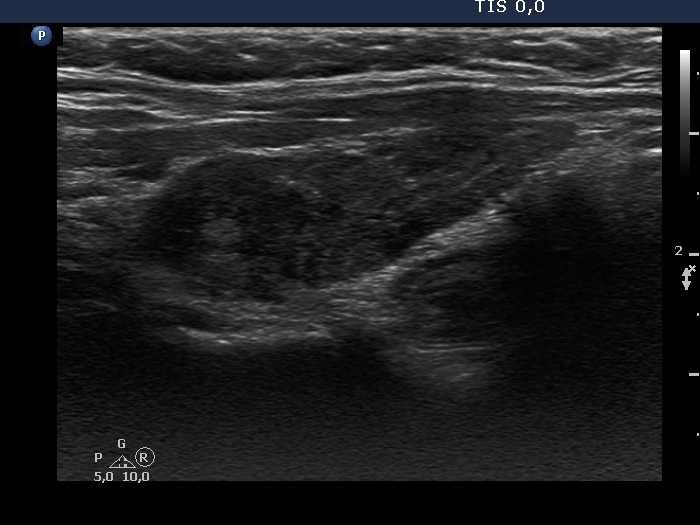

Consecutive patients with the final diagnosis of Hashimoto's thyroiditis - case 35 (1620) (ultrasonographic picture 6)

Left lobe, longitudinal view. There are echonormal islets within this lobe.